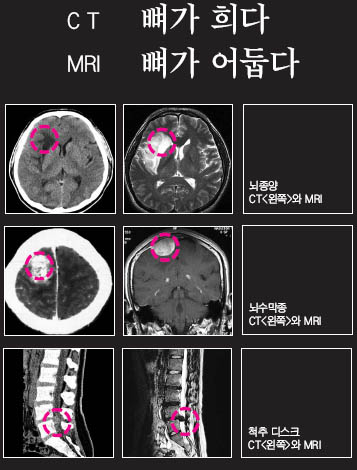

¹æ»ç¼±Àº »À¸¦ Àß Åõ°úÇÏÁö ¸øÇϹǷΠCT »çÁø¿¡¼­ »À ºÎºÐÀº Èñ°Ô º¸ÀÌÁö¸¸ MRI »çÁø¿¡¼± »À´Â ¾îµÓ°Ô, ¿¬ÇÑ Á¶Á÷Àº ¹à°Ô º¸ÀδÙ.

³ú¿¡ Á¾¾ç(Glioma)ÀÌ Àִ ȯÀÚÀÇ »çÁøÀ» º¸ÀÚ. ¿ÞÂÊÀº CT, ¿À¸¥ÂÊÀº MRI »çÁøÀÌ´Ù. CT»çÁøÀÇ ¿ÞÂÊ À­ºÎºÐ¿¡ ¾à°£ °Å¹«½º·³ÇÏ°Ô º¸ÀÌ´Â ºÎºÐÀÌ Á¾¾ç µ¢¾î¸®´Ù. CT´Â ³ú¸¦ µÑ·¯½Ñ µÎ°³°ñ ºÎºÐÀÌ Å׵θ®Ã³·³ ÇϾé°Ô º¸ÀÌ´Â ¹Ý¸é, MRI¿¡¼­´Â °Ë°Ô º¸ÀδÙ. MRI »çÁøÀ» º¸¸é Á¾¾ç µ¢¾î¸®ÀÇ Å©±â°¡ ²Ï Å©°Ô º¸ÀδÙ. CT¿¡¼­ ¹ß°ßÇÏÁö ¸øÇÑ Á¾¾ç±îÁö ´Ù ³ªÅ¸³­ °ÍÀÌ´Ù.

µÎ ¹øÂ°´Â ³ú¼ö¸·Á¾À» °¡Áø °°Àº ȯÀÚÀÇ CT¿Í MRI »çÁøÀÌ´Ù. CT»çÁø»óÀ¸·Î ¿ÞÂÊ À­ºÎºÐ¿¡ Ç㿸°Ô º¸ÀÌ´Â °÷ÀÌ Á¾¾çÀÌ´Ù. MRI»çÁøÀ» º¸¸é Á¾¾çÀÌ ³ú¸¦ µÑ·¯½Ñ ¸· ¹Ù±ù¿¡¼­ »ý°Ü ³ú ¾ÈÂÊÀ¸·Î ÀÚ¶ó´Â °ÍÀ» È®ÀÎÇÒ ¼ö ÀÖ´Ù. CT·Î´Â À̸¦ È®ÀÎÇϱⰡ ¾î·Æ´Ù. ¿¹¸¦ µé¾î ³ú¼ö¸·Á¾À» ¼ö¼úÇØ¾ß ÇÒ °æ¿ì¿¡ CT¸¸À¸·Î´Â ¾î·Æ°í, ¹Ýµå½Ã MRI¸¦ Âï¾î¾ß ÇÑ´Ù.

ôÃß µð½ºÅ© ȯÀÚÀÇ MRI»çÁøÀ» º¸¸é ¿äÃß 4, 5¹ø »çÀÌÀÇ µð½ºÅ©(Ãß°£ÆÇ)°¡ Æ¢¾î³ª¿Â °ÍÀÌ ¶Ñ·ÇÇÏ°Ô º¸ÀÌÁö¸¸ CT»çÁø¿¡¼­´Â µð½ºÅ©°¡ Æ¢¾î³ª¿Â °ÍÀÌ Èñ¹ÌÇÏ°Ô º¸ÀÏ »Ó ¾î´À Á¤µµ ½ÉÇÑÁö´Â Àß È®ÀεÇÁö ¾Ê´Â´Ù.